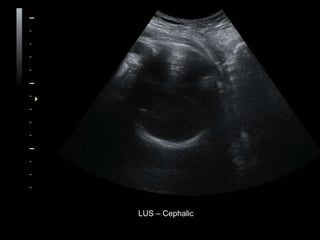

Dr. Ana Lourenco

HISTORY

• 36 yo female 30.5 weeks pregnant

• Referred with ‘multiple fetal anomalies’ for

fetal ultrasound

LUS – Cephalic

• What are the findings?

• What is the diagnosis?